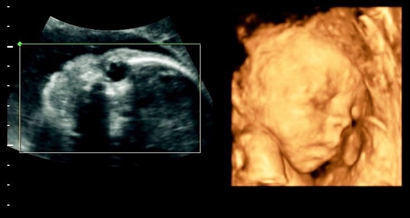

孕22周以上的胎儿各方面器官都已经渐渐成熟,胎儿的四肢以及生殖器官也已经形成,这时候做四维彩超是完全可以看到胎儿的生殖器官,从而判断胎儿的性别。不过也不是每个胎儿都那么配合做四维彩超的,有些胎儿的手刚好挡住关键部位,那么就没办法准确的判断胎儿的性别。

有人反应,做四维彩超的时候,医生明明说了是男孩,但是生出来却是女孩。其实,有些胎儿比较淘气,把手指放在两腿之间,那么做四维彩超的时候,有些医生就误以为是胎儿的生殖器官,然后就判断是男孩,那么生出来就肯定是女孩。所以,做四维彩超的报告单上面也写了,不是百分百准确的,有一定的误差。